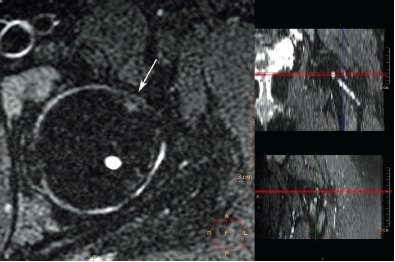

При анализе МРТ, выполненной на 19-м году жизни, установлено, что вышеописанная деформация перехода «головка – шейка» различной выраженности присутствовала в 25 (78,1%) из 32 суставов со смещением эпифиза, величина передневерхнего угла α при этом варьировала в диапазоне от 46° до 71°, в среднем 60,6±7,7° (рис. 3, 4).

Рис. 3. МРТ левого тазобедренного сустава пациентки 18 лет 2 мес. через 4 года 7 мес. после операции, косая аксиальная проекция, Т2-взвешенное изображение. Деформация перехода «головка – шейка» (обозначена стрелкой) — отсутствие нормальной вогнутости перехода и увеличенный передневерхний угол α — 87,4 °